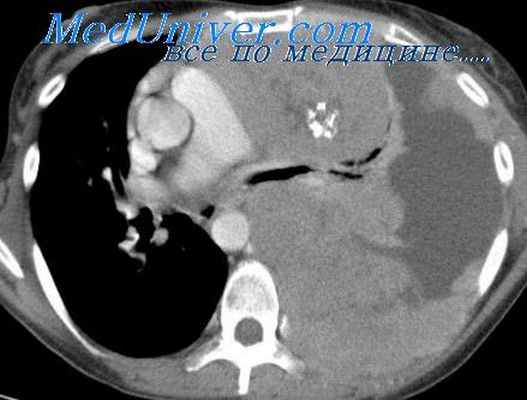

Компьютерная томография помогает уточнить размеры и локализацию тимомы, выявить небольшую опухоль, которая не обнаруживается во время рентгенографии. Увеличение тимуса на снимках, полученных с помощью КТ, также чаще всего свидетельствует о том, что в вилочковой железе присутствует тимома.

Компьютерная томография предпочтительна у пациентов с миастенией. Наиболее информативны снимки, выполненные с внутривенным контрастированием. Они помогают оценить расположение тимомы по отношению к крупным кровеносным сосудам, ее кровоснабжение, правильно спланировать операцию.

Компьютерная томография с контрастированием — более информативный метод. Он позволяет получить информацию о наличии новообразования, определить его злокачественность, и даже дифференцировать его природу — отличить тимому от лимфомы и др. МРТ не является рутинным методом диагностики тимом, но может использоваться по показаниям, например, при наличии у пациента аллергии на йодсодержащий контраст, применяемый при КТ.